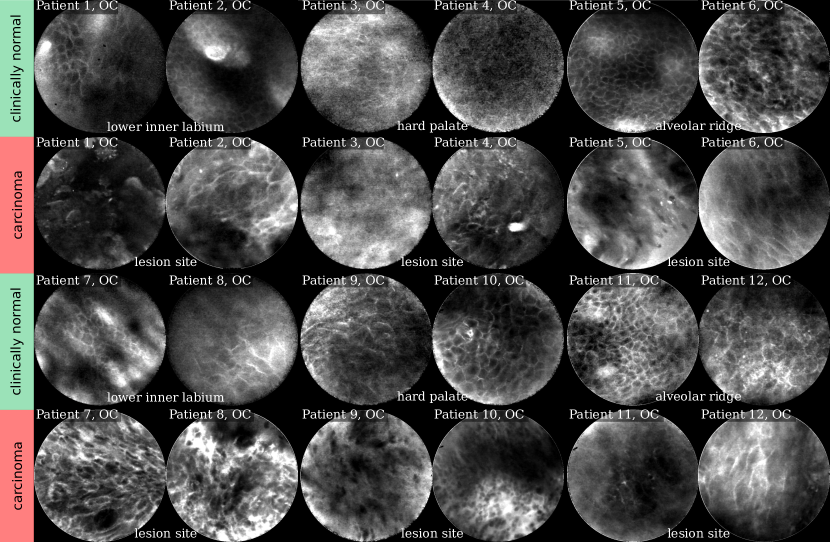

Refer to caption

Figure 3: Selected CLE Images acquired from the vocal fold area. In the top row, presumably healthy images are depicted that were taken from the clinically normal contralateral vocal cord of patients with epithelial cancer one of the both vocal cords (shown in the bottom row). Note that for patient 5, only images showing clinically normal tissue were available.

For this work, 47 image sequences from five patients were recorded. All patients underwent biopsy subsequent to CLE and were diagnosed with SCC of the vocal folds using the gold-standard of histo-pathology. The images of this data set have been acquired during micro-laryngoscopy at the Department of Otorhinolaryngology, Head and Neck Surgery (University Hospital Erlangen). The study was approved by the IRB of the University of Erlangen-Nürnberg (reference number: 60_14 B). For each patient, the contra-lateral vocal cord that was in each case macroscopically unaffected was also recorded, building a data set representing presumably healthy tissue of the vocal folds. For one patient (patient 5, see Fig. 3), no sequences with histo-pathology-confirmed SCC were available when this data set was created.

Comparing the images in Figures 2 and 3, for clinically normal (and presumably healthy) tissue we find a large difference in contrast for some regions. While for images acquired from the alveolar ridge (rows 1 and 3, columns 5 - 6 in Fig. 2) and the vocal folds (top row in Fig. 3), contrast is generally good and cell outlines can be clearly spotted for most images, we find a much broader spread in image quality for images acquired at the hard palate and the lower inner labium (rows 1 and 3, columns 1-4 in Fig. 2).